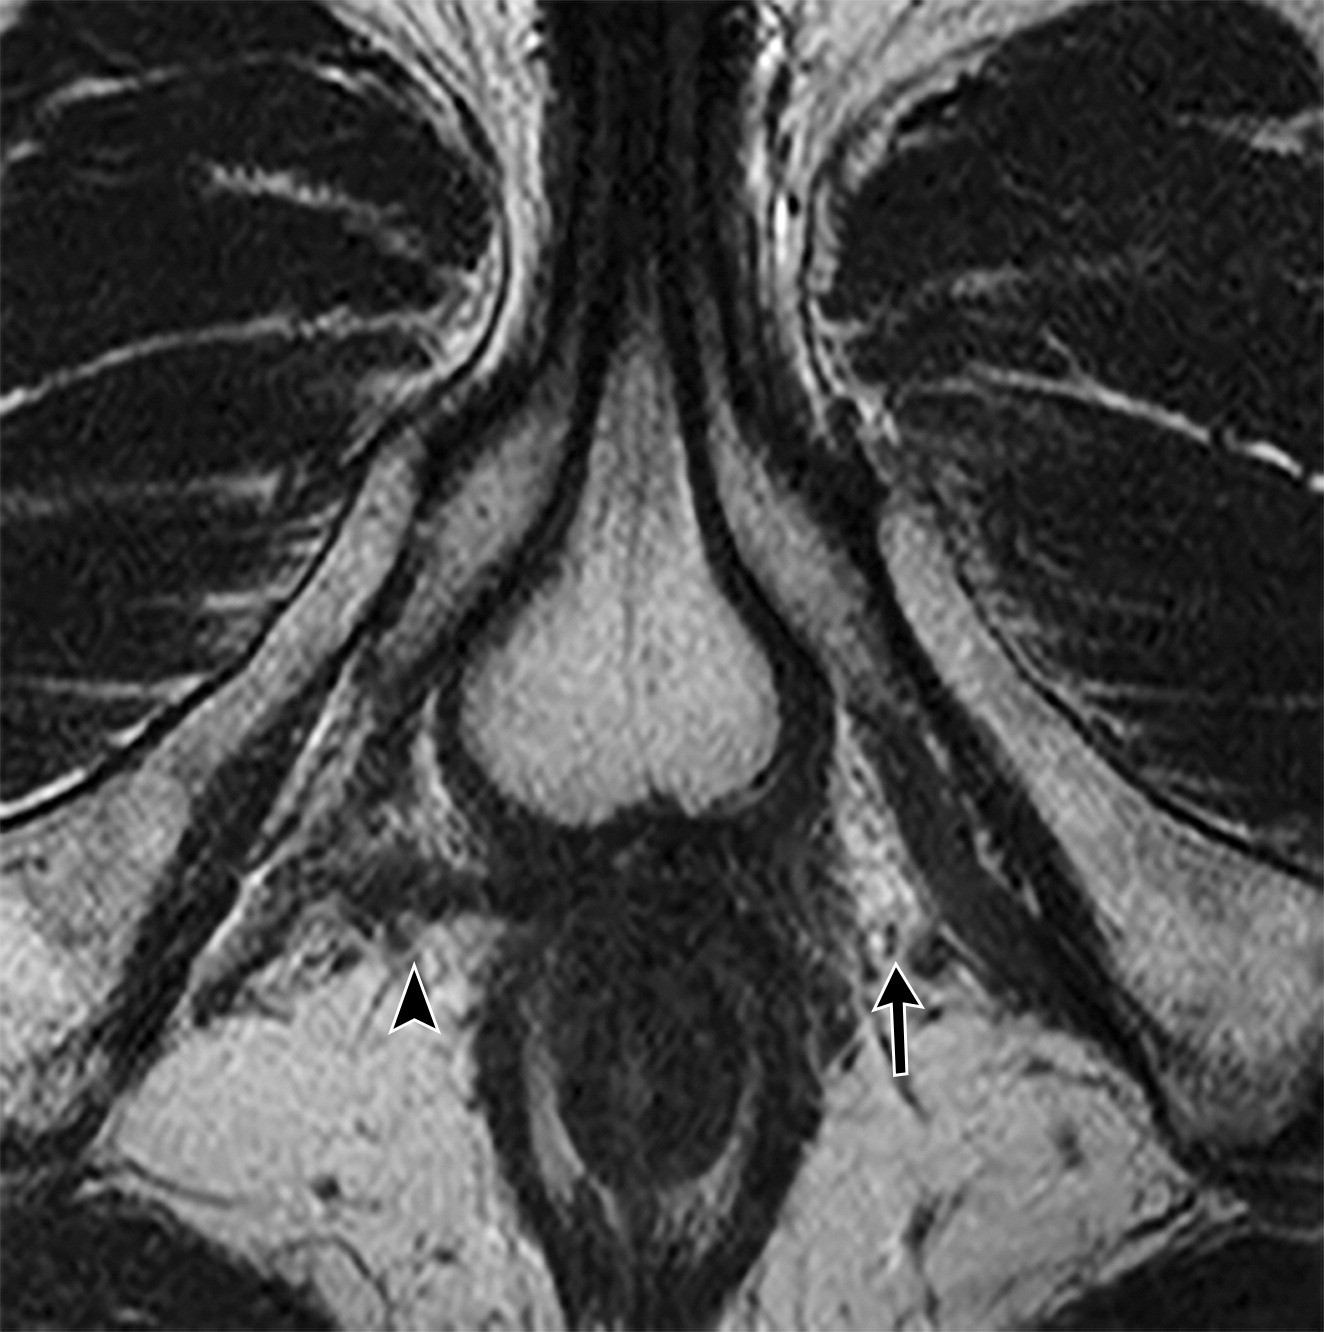

尿道吊带。

白色长箭头示尿道吊带的正常位置,正常的尿道吊带是薄的T2WI低信号影,向外延伸至闭孔。